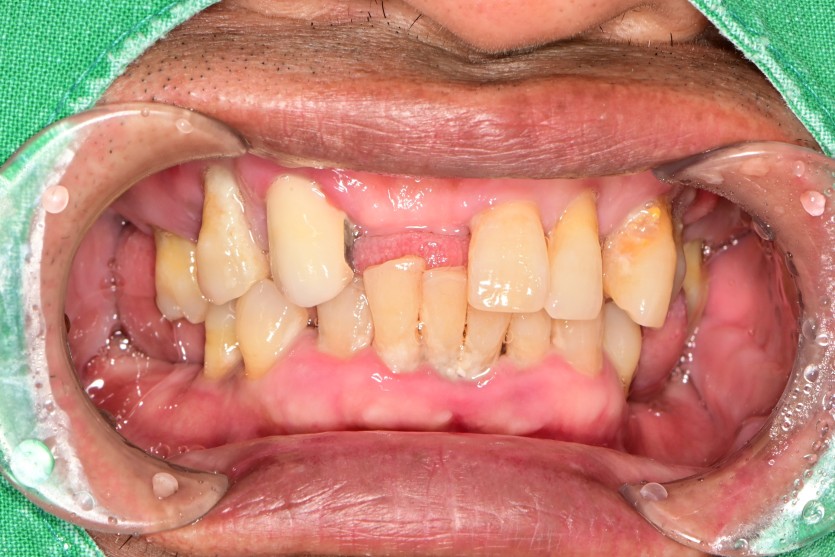

풀아치 증례입니다.

6개의 임플란트로 완성하였습니다.